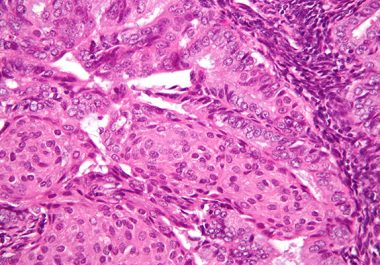

Lorazepam used to relieve stress may cause inflammation that promotes tumor growth and shortens progression-free survival, study says. A medication commonly used to ease the stress caused by cancer diagnosis and treatment may be...